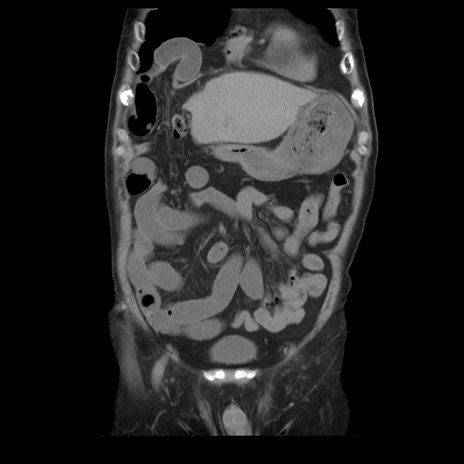

横断像

【症例】70歳代男性

【主訴】腹痛

【現病歴】肝硬変・肝細胞癌にてかかりつけの方。約9時間前に食後より腹痛出現。症状が徐々に増悪し、嘔吐出現したため来院。

【既往歴】肝硬変、肝細胞癌(RFA、TACE後)

【身体所見】意識清明、表情苦悶様、BT 36℃、BP 129/78mmHg、P 88bpm、SpO2 97%(RA)、右上腹部から心窩部にかけて圧痛あり、反跳痛なし、筋性防御あり。

【データ】WBC 5800、CRP 0.16